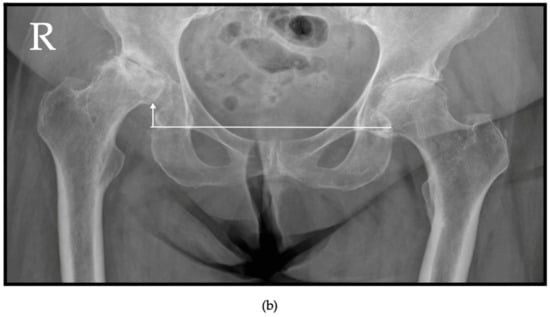

4.2.3. Sagittal Spinopelvic Malalignment

- Orita, K.; Okuzu, Y.; Shimizu, T.; Goto, K.; Kuroda, Y.; Kawai, T.; Matsuda, S. Investigating sagittal spinopelvic alignment and equivalent stress on the femoral head in patients with rapidly destructive coxarthrosis. Eur. J. Orthop. Surg. Traumatol. 2024, 34, 901–908. [Google Scholar] [CrossRef]

- Nakamura, K.; Okamoto, Y.; Wakama, H.; Matsuyama, J.; Ishitani, T.; Otsuki, S.; Neo, M. T1 pelvic angle is associated with rapid progression of hip arthrosis. Eur. Spine J. 2023, 32, 1463–1470. [Google Scholar] [CrossRef]